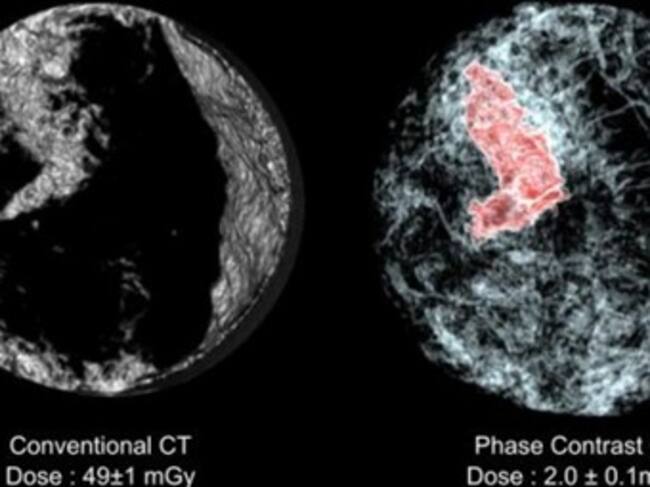

Escáner capaz de diagnosticar un tumor de forma exacta y con la mitad de dosis de radiación, se presentó en Chicago.

"Es un método nuevo de medicina nuclear que pasa de los tubos (de rayos) catódicos, como las antiguas radios o televisiones, a una imagen digital que recoge cada fotón que se emite del enfermo, del tumor, y que supone un adelanto bastante grande", afirmó a Efe Ros, quien subrayó que la radiología preventiva "salva vidas"